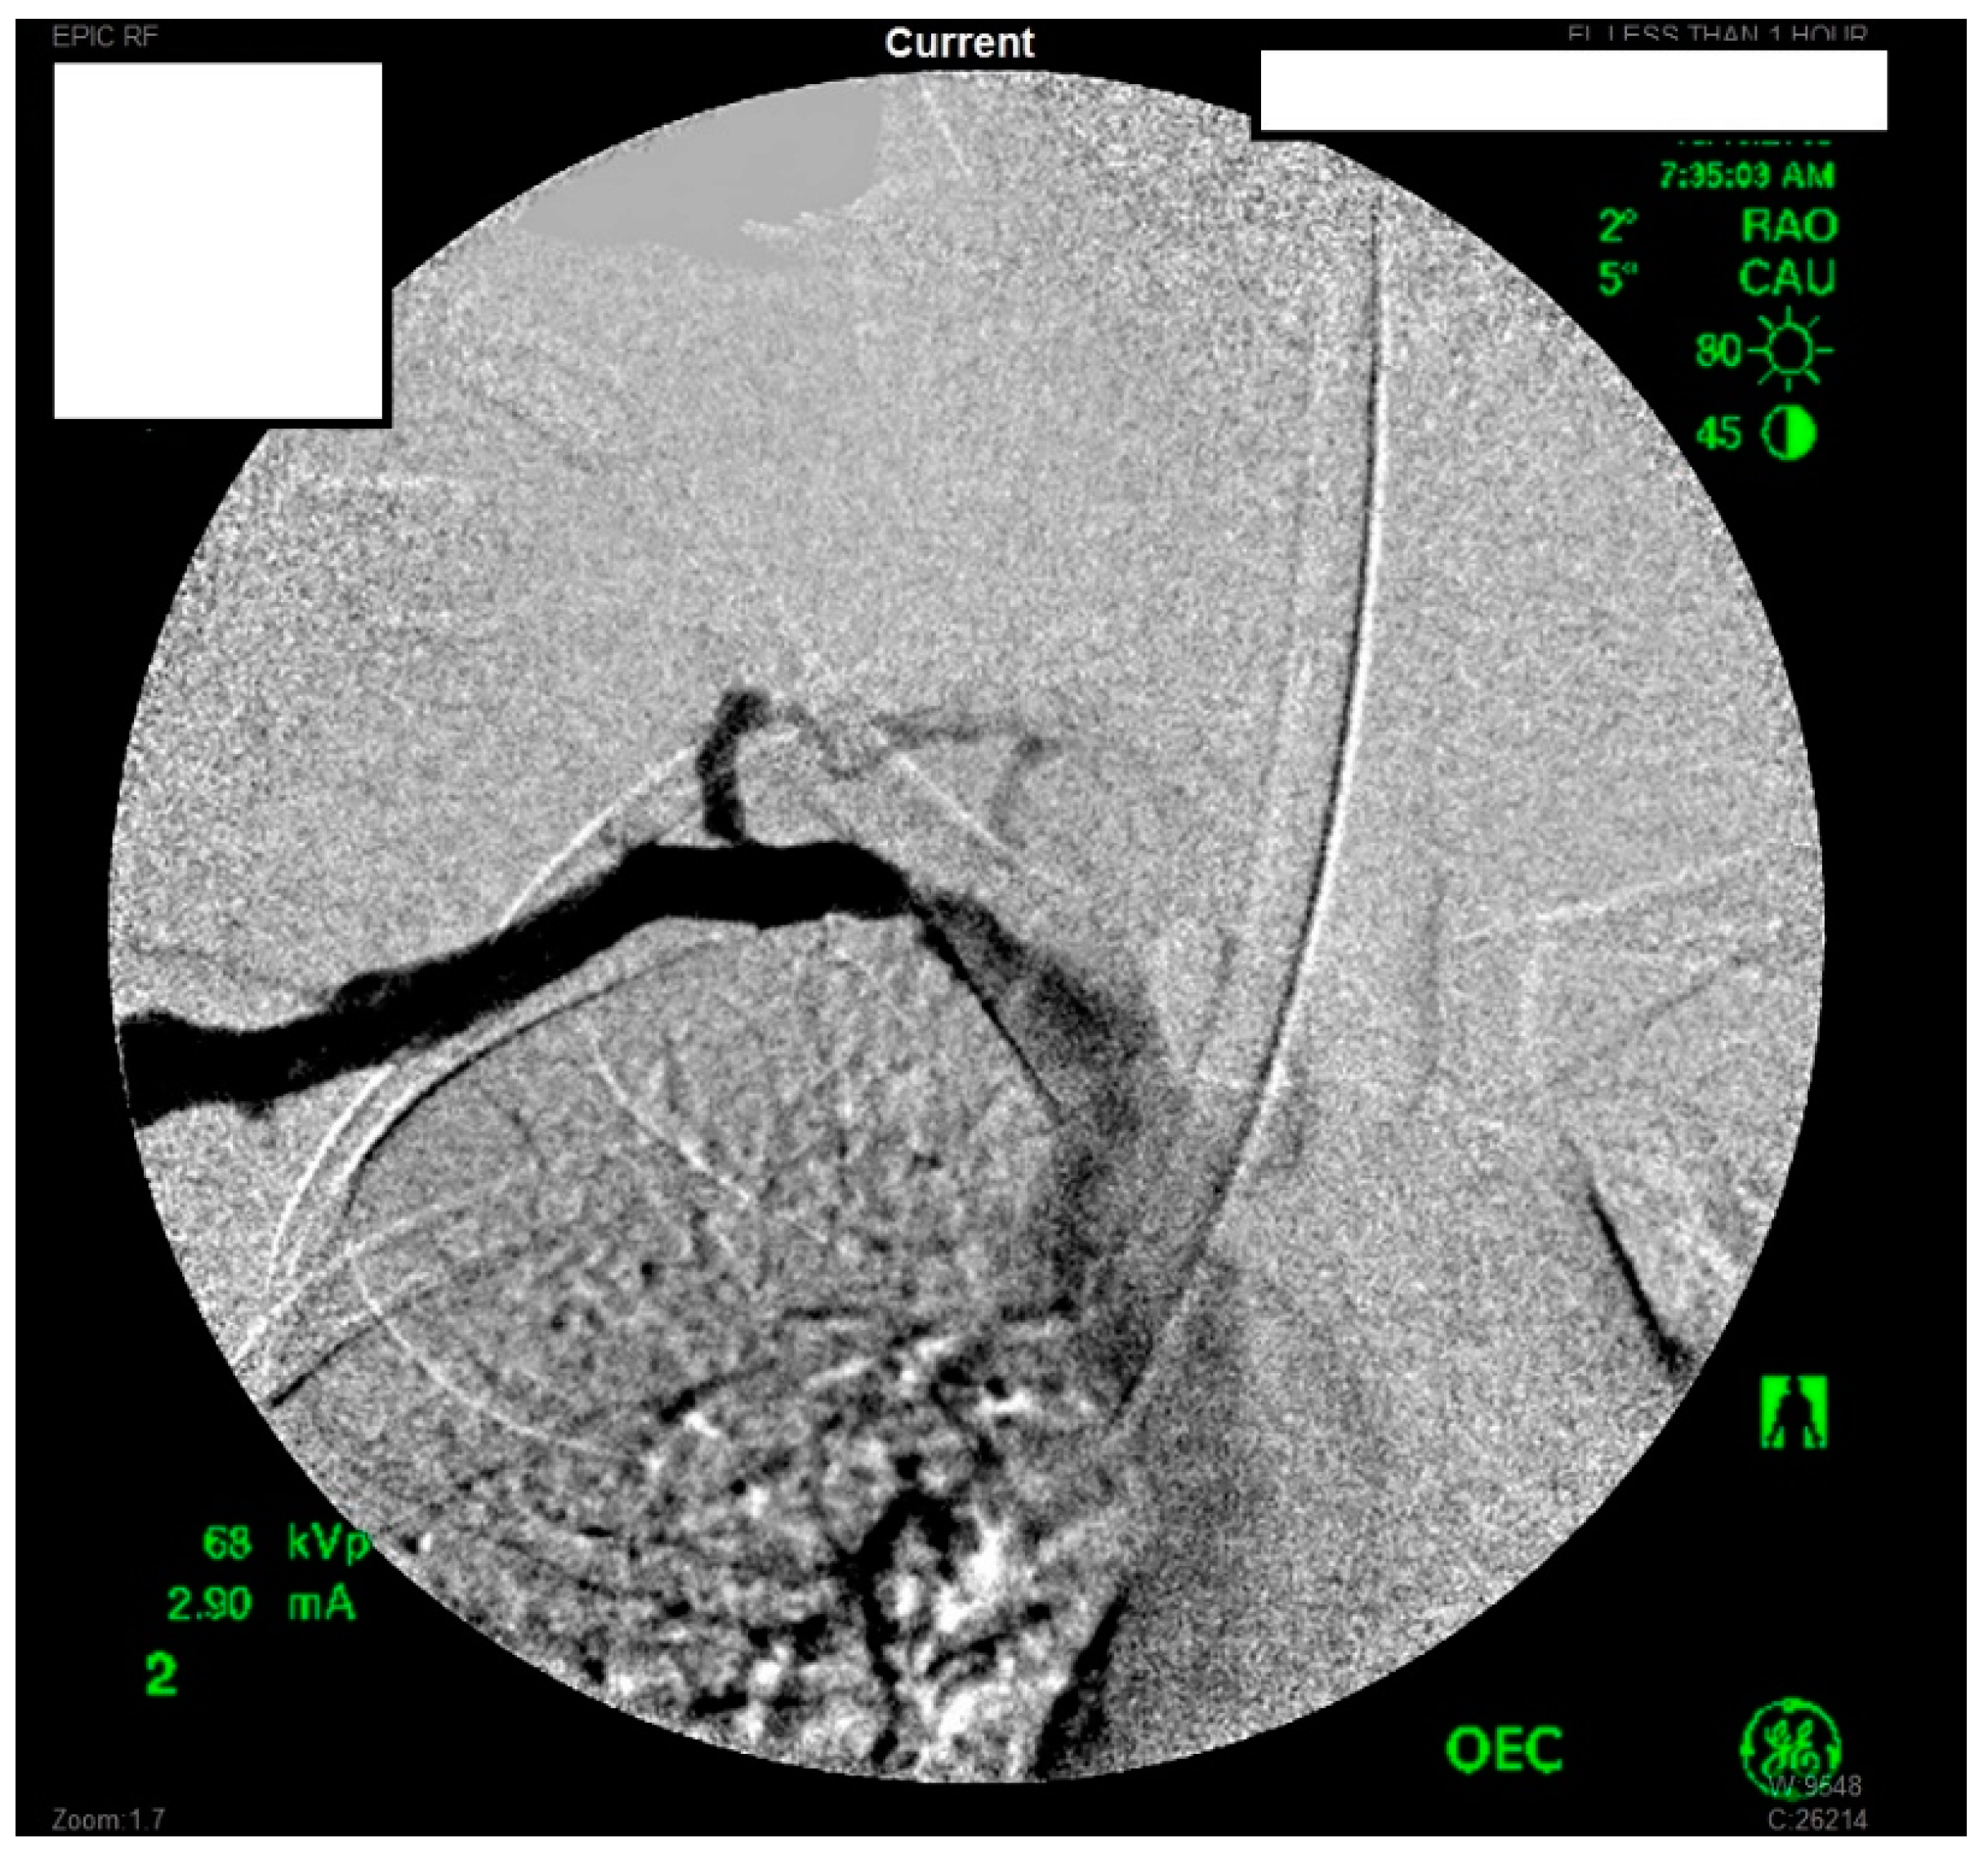

She underwent venography of the right arm venous system which revealed a 70–80% stenosis of the right subclavian vein in neutral position (Figure 1 and Figure 2). The vein was completely occluded in stress position. This was confirmed with intra-vascular ultrasound (IVUS). On IVUS measurements, the neutral position yielded a 74.4% stenosis while the stress position yielded 100% total occlusion (Figure 3 and Figure 4). It was noted that the contralateral vein appeared compressed in the costochondral space as well, though she was asymptomatic.

Figure 1.

Venogram of a Paget-Schroetter patient in the stress position demonstrating significant stenosis of the right subclavian vein.